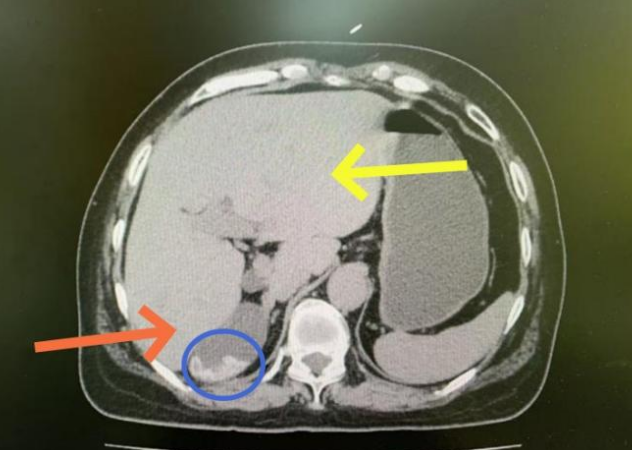

接诊入院后,经过了专业检查,结果令所有人大吃一惊:陈女士的右肝在CT上几乎找不到了,左肝比却要比常人大出几倍!

仔细读片后发现她的右肝管主干上长满了结石,导致右肝胆汁无法排出,因长期废用导致右肝逐渐萎缩,而左肝代偿性增大引发的肝“萎缩-肥大综合征”。郑志鹏解释道:“萎缩-肥大综合征”肝脏对局部血流或胆汁引流受阻所产生的代偿-萎缩性形态学组合,这种结石梗阻胆道的萎缩非常容易恶变,相当于一个定时炸弹,必须积极手术治疗。